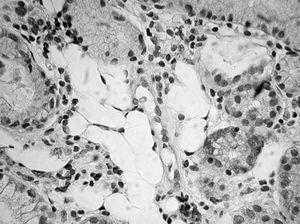

Fig. 1. Espacios vacíos en la lámina propia, similares a grasa. (Hematoxilina-eosina,*100.)

Presentamos el caso de una mujer de 70 años, diagnosticada 6 años antes de gastritis crónica con metaplasia intestinal, que en una gastroscopia de control mostraba una mucosa gástrica adelgazada y de aspecto atrófico; en el estudio microscópico de las biopsias llamaban la atención unos espacios claros similares a tejido adiposo situados en la lámina propia, de entre 30-200 µ, que se disponían entre las glándulas y continuaban hacia la muscular de la mucosa y submucosa (fig. 1). Estas vacuolas no mostraban revestimiento epitelial ni endotelial, y tampoco existía una reacción inflamatoria, gigantocelular o fibrosa en su vecindad. No mostraban tinción con ácido paraaminosalicílico ni azul alcián, y tampoco inmunorreactividad con los anticuerpos S-100 y CD34. El diagnóstico fue de seudolipomatosis gástrica. La biopsia mostraba además una gastritis crónica atrófica con metaplasia intestinal y abundantes Helicobacter pylori.